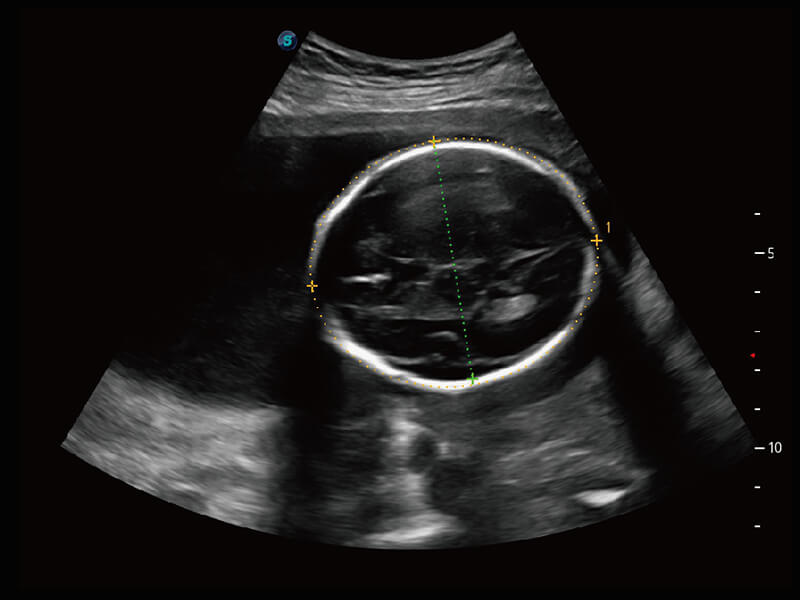

彩色多普勒超声诊断系统

S60探头工艺,从前端信号处理每一个环节采集无损声学数据,真实还原组织原貌,再现解剖细节。

超宽频带技术,为容积成像带来优质的二维图像基础,为您呈现丰富的结构细节,栩栩如生地展示宝宝的宫内形态以及各种组织的立体结构。